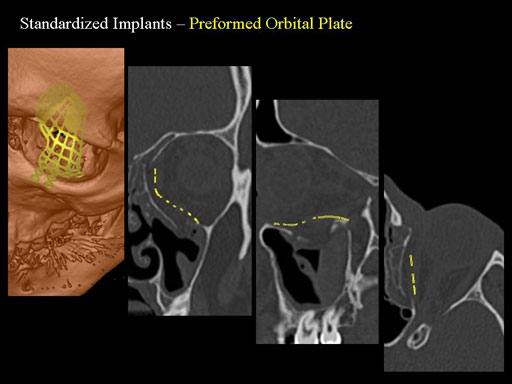

Unlike the existing two-dimensional mesh implants, the geometry of the new preformed plates will be adequate to match the individual anatomic situation of the patient in almost any case. However, the mesh parts can be individually adjusted if necessary. In these cases the solid part in the central posterior area needs to remain untouched. Areas of the orbit that do not require a bridging can be spared out by trimming the implant along the designated cutting lines in the height of the medial wall and/or length of the orbital floor area. The lateral anterior part of the plate is intentionally pre-bent higher than the orbital rim anatomy to allow free plate movement during plate positioning.

The Preformed Orbital Plates are indicated for trauma repair and reconstruction of fractures of the orbital floor, medial orbital wall or combined fractures of floor and medial wall. It should be noted that in three-wall fractures where the lateral wall is also involved, a second orbital implant, ( i. e. the mesh plate) must be used in addition to the pre-formed orbital plate.

Implant placement according to the orbital landmarks

1 Orbital rim, 2 Inferior orbital fissure, 3 Posterior orbital ledge, 4 Transition between the medial wall and orbital floor, 5 Optic canal, 6 Lacrimal fossa